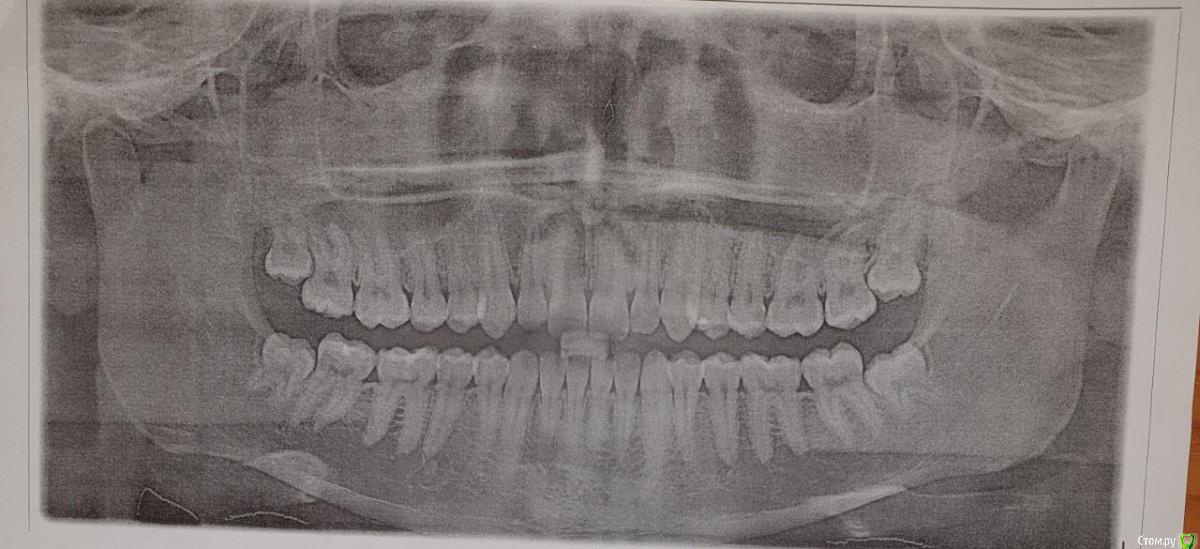

Стал фиксировать убыль на фотографиях, которые приложу к данному посту. Также прикладываю результаты анализов. Помимо этого полгода назад делали панорамный снимок, который вроде как показал, что убыли костной ткани нет. На вопрос а в чем тогда проблема, мне ответили, что это просто рецессия (видимо, так задумано и все ок, пока зуб не выпадет подождем).